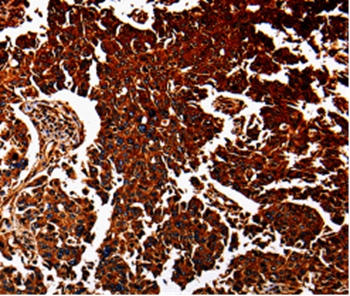

Immunohistochemical analysis of paraffin-embedded Human renal cancer tissue using #35568 at dilution 1/40.